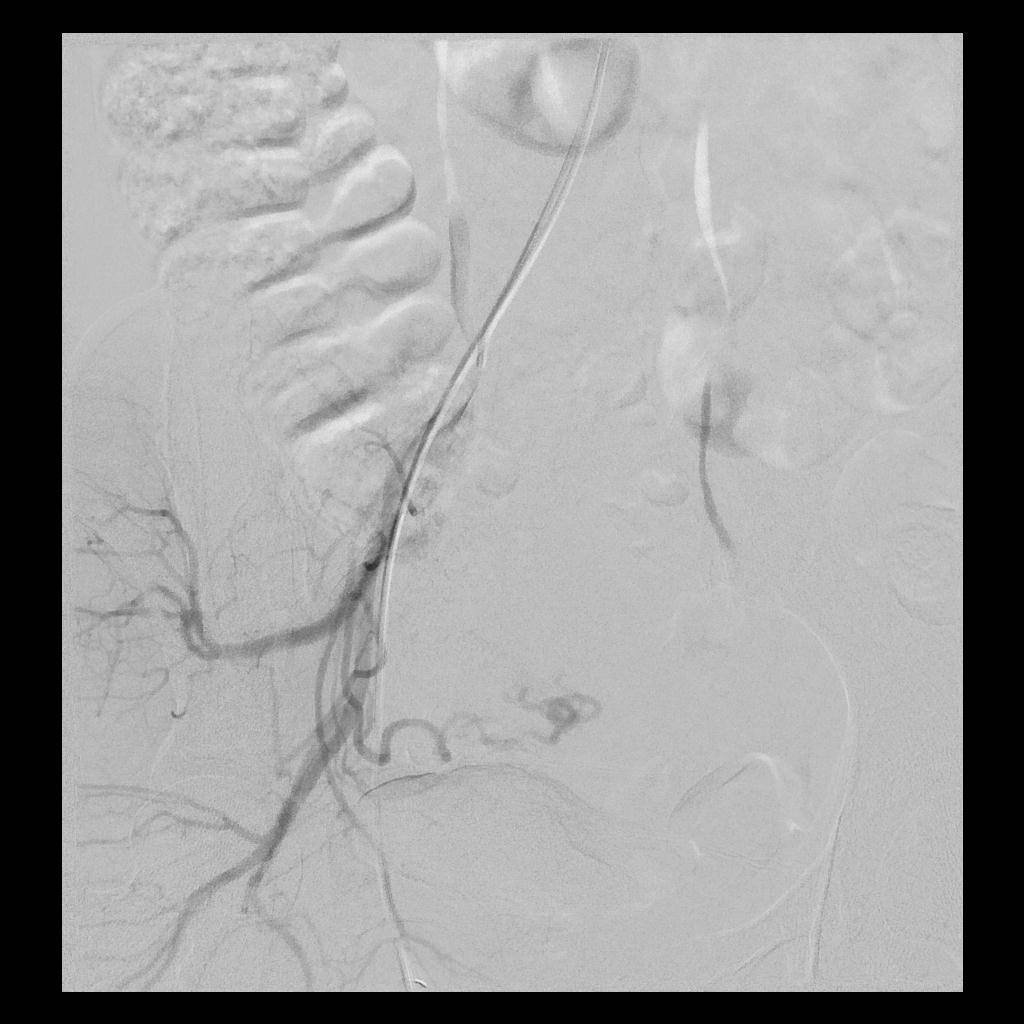

后经腹部主动脉造影显示,子宫双侧的子宫动脉均有增粗、迂曲的情况(下图中红色箭头所示),子宫和子宫肌瘤也均有所增大(下图中绿圈所示)